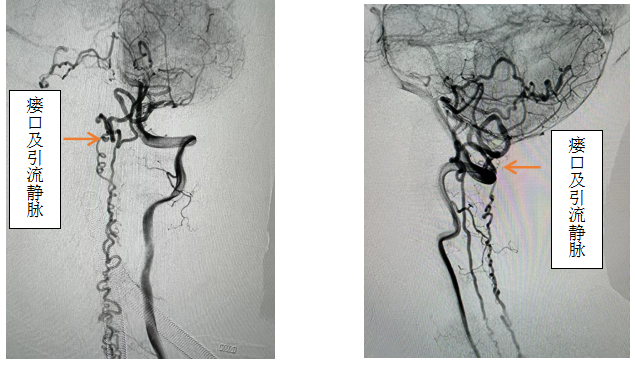

患者女性,56岁,以“双下肢无力伴感觉异常半年,加重2月”主诉入院,入院前先后辗转我省多家医院,效果欠佳。入院时已经行走困难,行颈椎核磁见颈椎蛛网膜下腔异常信号影,请神经外科会诊后考虑硬脊膜动静脉瘘可能性大,转入神外后立即由李帅主治医师行全脊髓血管造影,见“左侧椎动脉V4段发出脑膜支,其远端分支供血形成硬脊膜动静脉瘘,瘘口位于枕骨大孔区,经延髓背侧及腹侧向下引流至胸2椎体节段”。缪星宇主任主持全科病例讨论,讨论考虑患者经脊髓血管造影后诊断明确,手术指征明确,可行硬脊膜动静脉瘘介入栓塞术或开颅阻断术。术中可采取“高压锅”技术防止栓塞胶的返流,降低微导管的到位要求,降低返流空间的要求,使得返流空间安全可控,缩短注胶时间,增加胶的弥散效率,从一定程度上提高栓塞比例,增加患者的安全性。如介入微导管到位困难,可以考虑开颅阻断瘘口,但瘘口位置距离呼吸中枢延髓较近、术中风险大且术后患者恢复时间长。科室讨论后决定利用六合彩网站

先进的复合手术室,首先采用第一方案“高压锅”技术使胶完全封堵瘘口,若不能到位或完全封堵,则采用第二方案,转为开颅阻断瘘口。手术当日,由黄卫东主任医师和李帅主治医师操作,第一根栓塞微导管顺利到达瘘口,第二根微导管接近栓塞微导管后使用弹簧圈顺利形成高压锅塞子,经第一根微导管注入栓塞胶,射线透视下见栓塞胶按预期流向瘘口,栓塞满意后造影示瘘口及引流静脉均未见显影,手术成功。术后患者恢复良好,第二天即下床活动,下肢活动明显恢复,5天后步行出院。